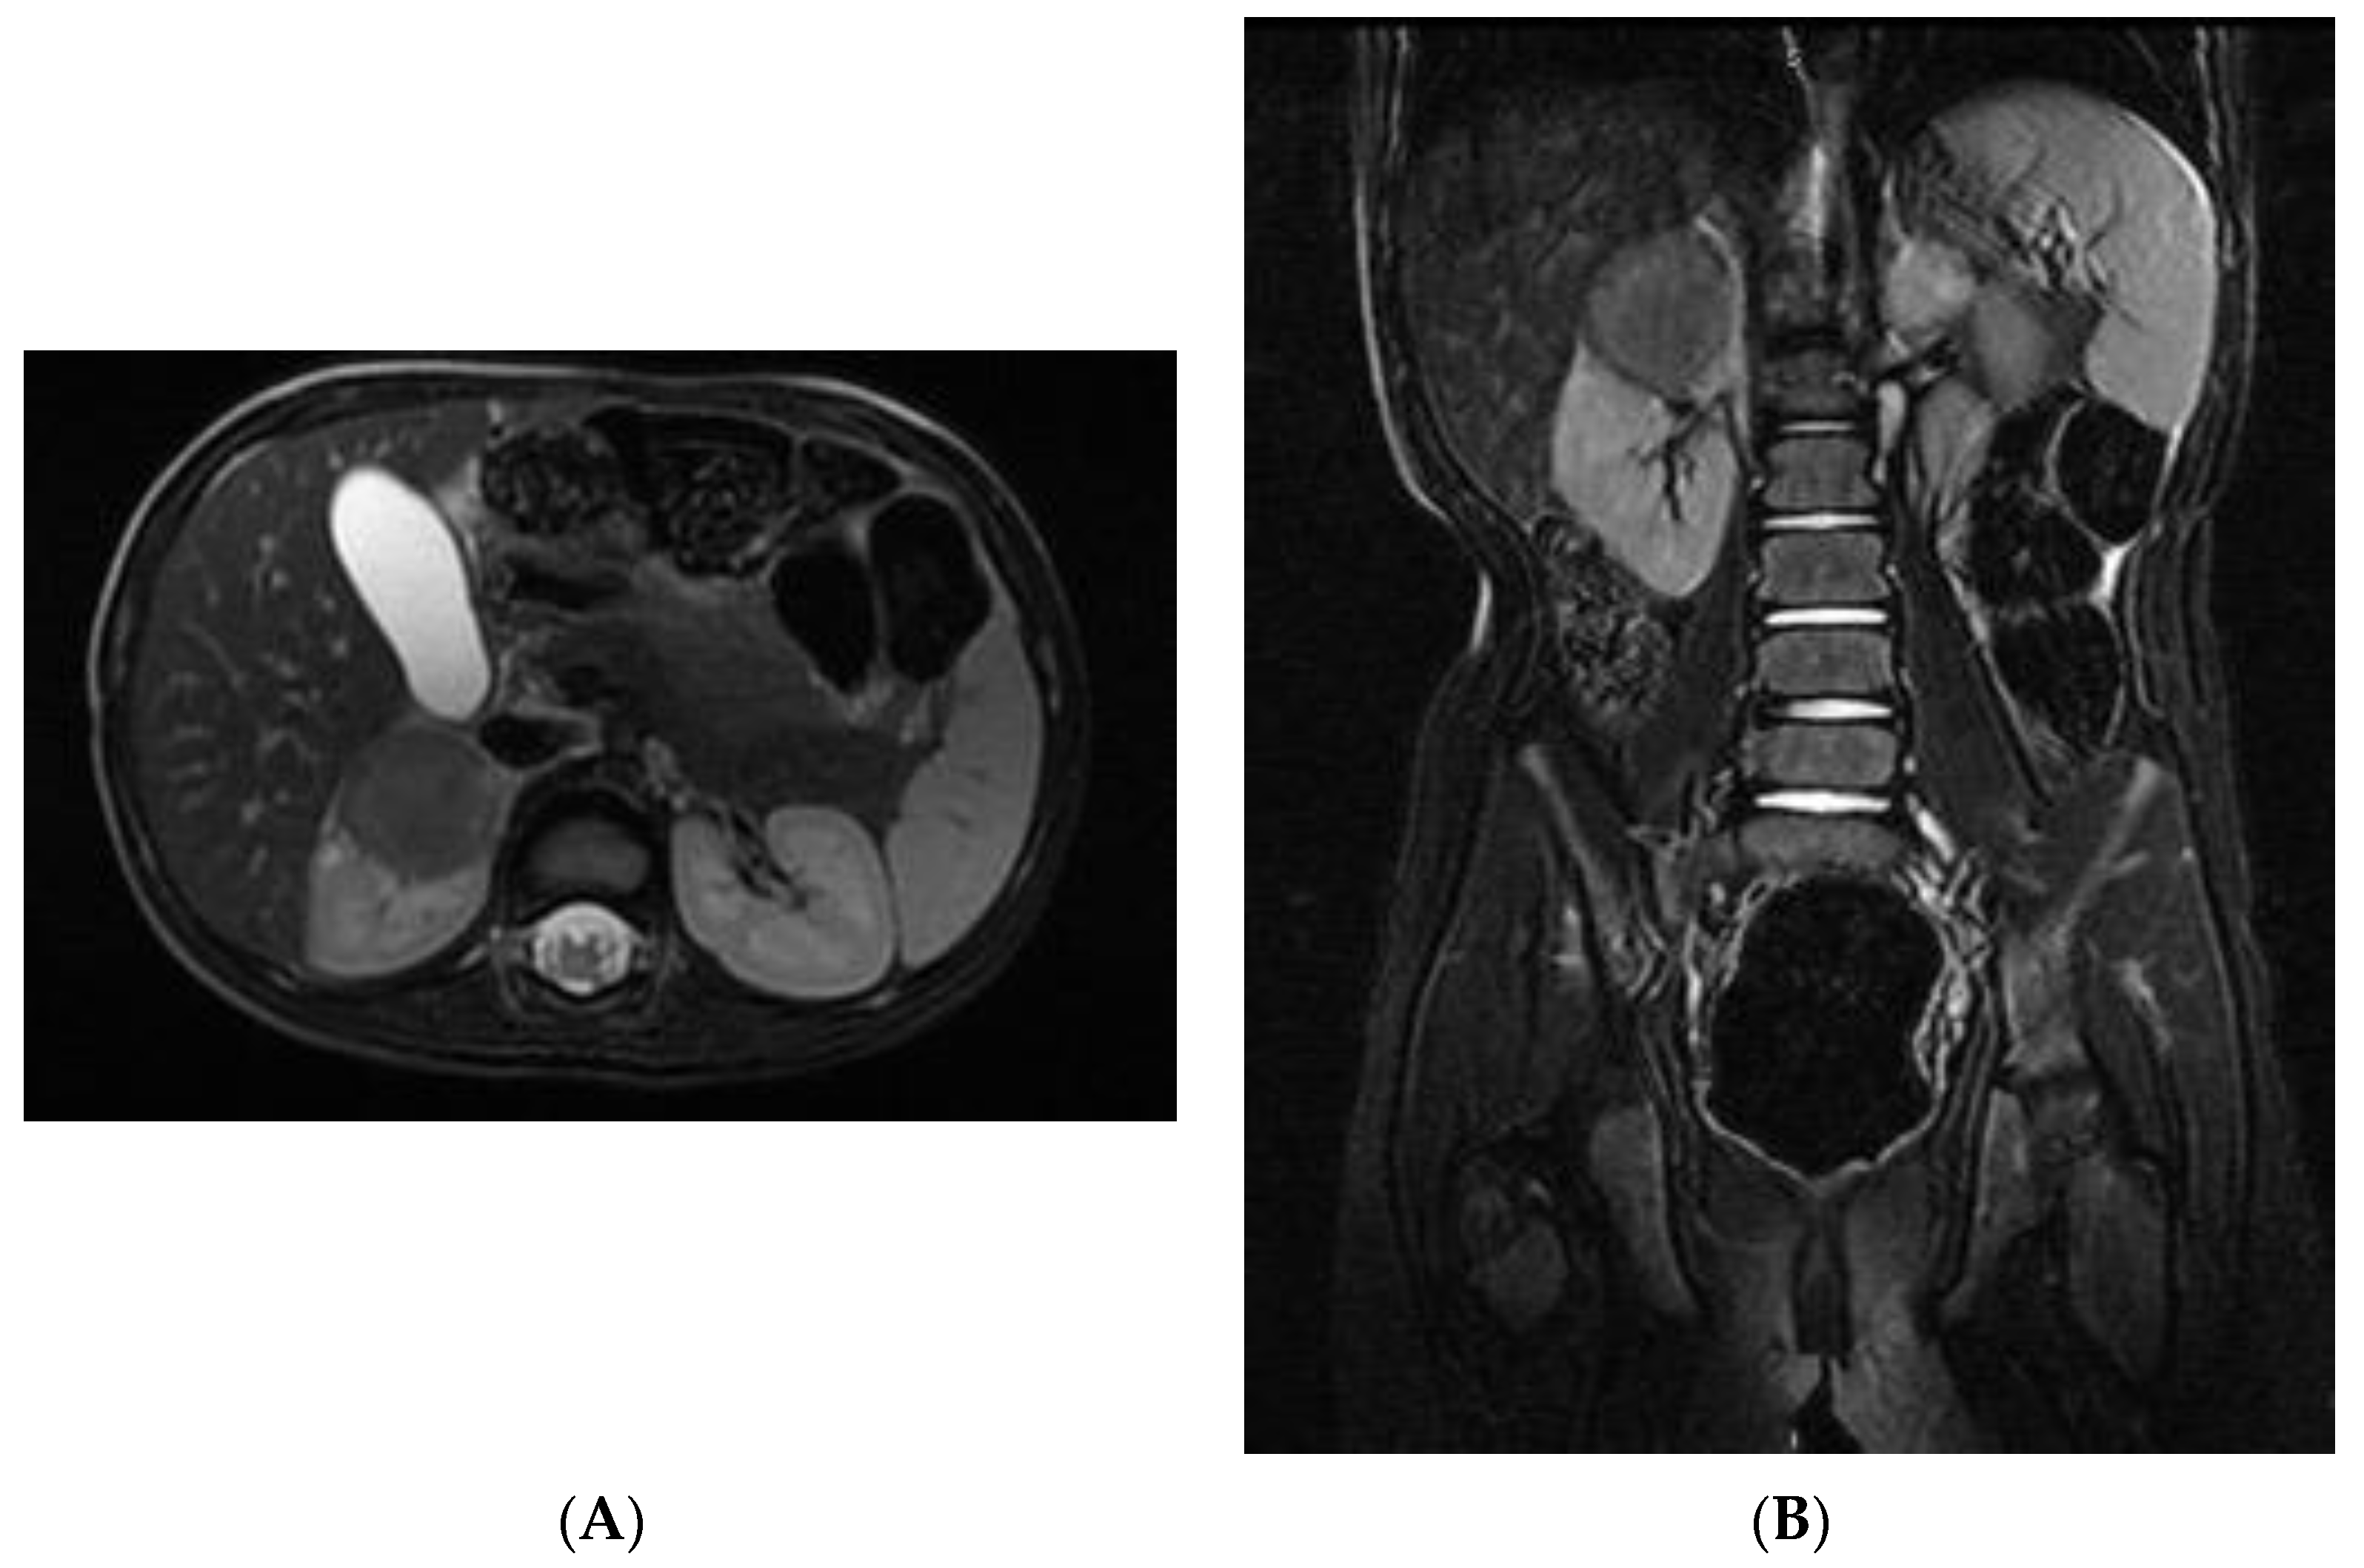

2. Case Report